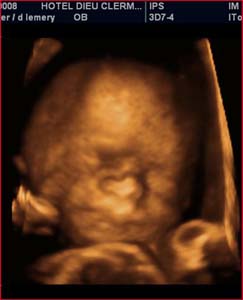

Analyse 3D : Echographie temps réel